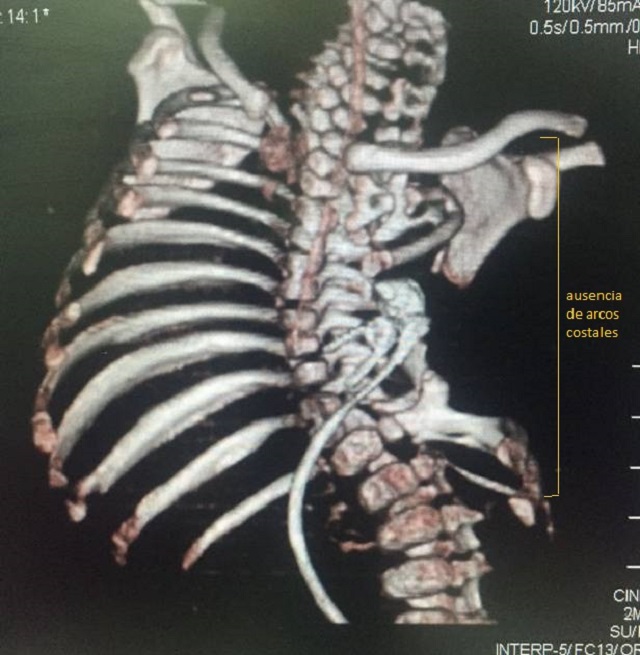

El niño, que actualmente tiene dos años y otras complicaciones de salud, fue diagnosticado al nacer con un síndrome genético que causa malformaciones en las costillas y vertebras conocido como Jarcho-Levin.

En su caso particular se evidenció la ausencia de sus costillas del lado izquierdo y de los músculos de la pared torácica, que le ocasionaban dificultad respiratoria severa.

El síndrome de Jarcho-Levin es una patología rara de incidencia mundial baja estimada de 1 en 200.000 recién nacidos vivos con variación geográfica marcada, definida como una anomalía en el desarrollo de los huesos, de carácter hereditario, caracterizada por grados variables de malformaciones, que en el tiempo se ha conocido con diversos nombres.